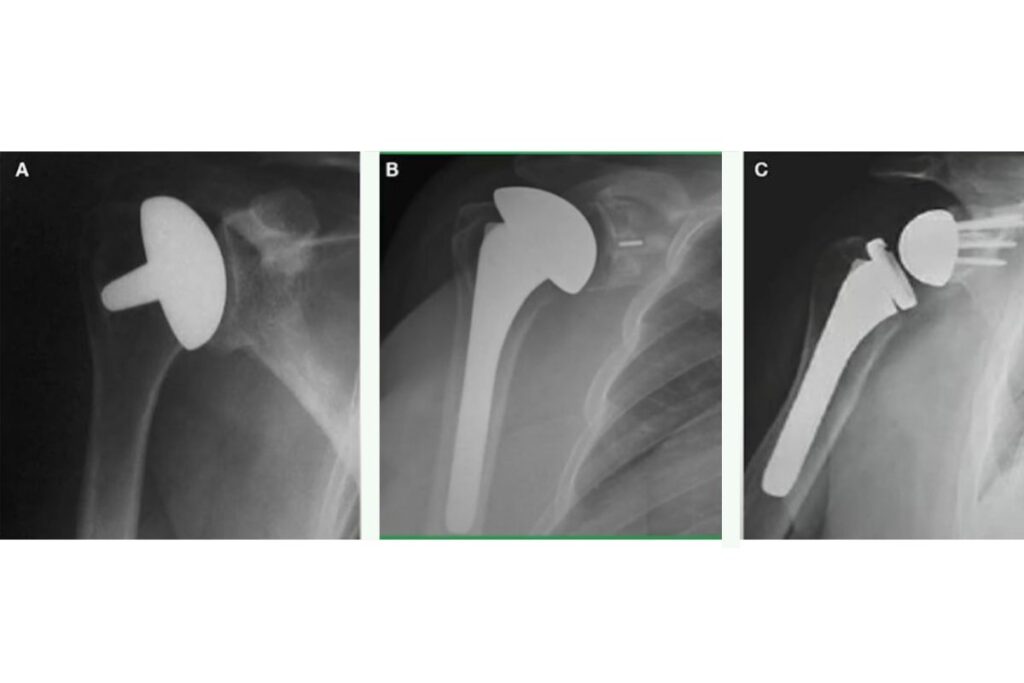

Classificamos as próteses de ombro em três tipos principais, cada uma adequada a diferentes condições clínicas, confira abaixo:

Prótese parcial do ombro

Nesta abordagem, substituímos apenas a cabeça do úmero por um componente, preservando a glenoide natural.

Indicamos quando a superfície da glenoide está relativamente intacta, como em certos casos de fraturas complexas do úmero proximal ou necrose avascular da cabeça umeral.

Prótese total anatômica do ombro

Este tipo de prótese substitui tanto a cabeça do úmero quanto a glenoide, replicando a anatomia natural da articulação.

Recomendamos para pacientes com artrose primária do ombro que possuem um manguito rotador funcional e íntegro.

Prótese reversa do ombro

Nesta configuração, fixamos a esfera metálica na glenoide e colocamos a cavidade no úmero, invertendo a anatomia normal.

Essa inversão altera a biomecânica do ombro, permitindo que o músculo deltoide assuma a função de elevação do braço em pacientes com lesões graves ou irreparáveis do manguito rotador.